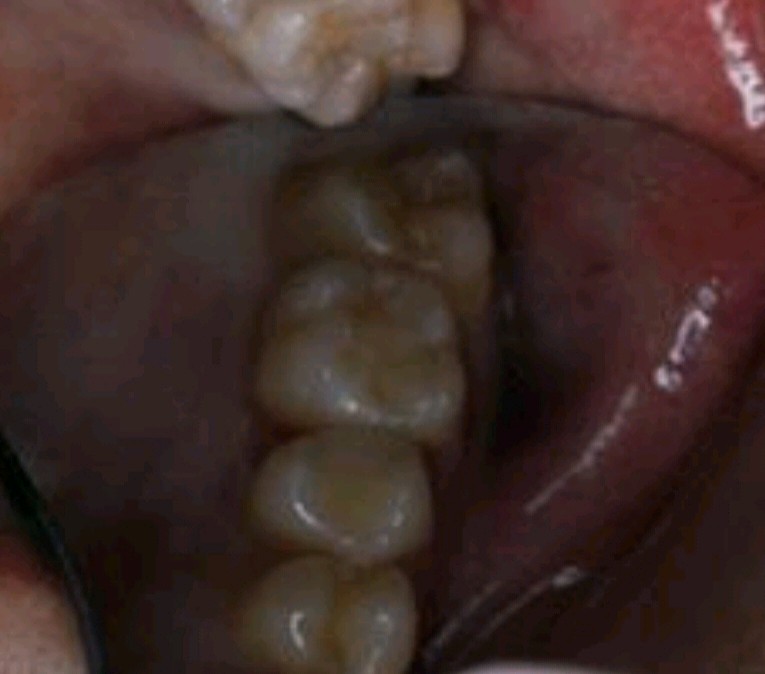

术后

图片发自160App